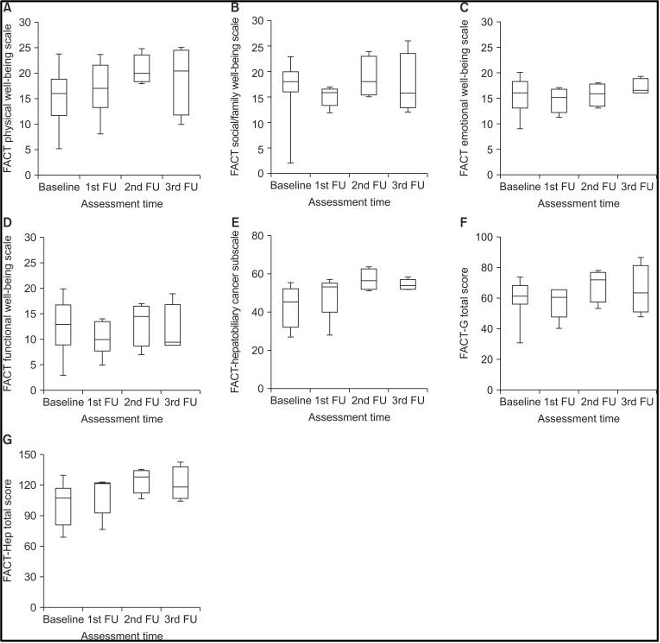

לא נמצאו הבדלים מובהקים באיכות החיים הקשורה לבריאות (HRQoL) בזמן ההערכה במטופלים שיכלו לענות על השאלון, הן EORTC QLQ-C30 (איור 3) והן FACT-Hep (איור 4). ציוני איכות החיים הקשורים לבריאות (HRQoL) נטו בדרך כלל להשתפר עם המעקב. עם זאת, סטטוס הבריאות הגלובלי (global health status) וסולמות הסימפטומים (symptom scales) של EORTC QLQ-C30 ירדו מעט במהלך המעקב.

להלן איור 4: שינויים ב-FACT-Hep, תתי סולמות מקו הבסיס ל3 חודשים לאחר טיפול קרינתי לכל הכבד בשילוב עם היפרתרמיה. (A) רווחה גופנית, (B) רווחה חברתית ומשפחתית, (C) רווחה רגשית, (D) רווחה תפקודית, (E) hepatobiliary cancer subscale, (F) FACTGeneral, (G) FACT-Hep total scores

לא נמצאו הבדלים מובהקים באיכות החיים הקשורה לבריאות (HRQoL) בזמן ההערכה במטופלים שיכלו לענות על השאלון, הן EORTC QLQ-C30 (איור 3) והן FACT-Hep (איור 4). ציוני איכות החיים הקשורים לבריאות (HRQoL) נטו בדרך כלל להשתפר עם המעקב. עם זאת, סטטוס הבריאות הגלובלי (global health status) וסולמות הסימפטומים (symptom scales) של EORTC QLQ-C30 ירדו מעט במהלך המעקב.